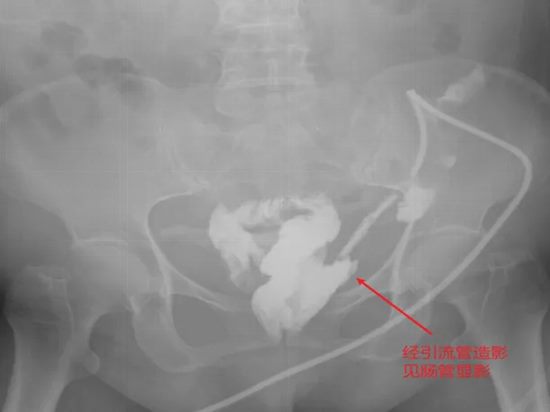

病情简述:患者胰十二指肠术后并发胆瘘、胰瘘、肠瘘,外院四次清创仍无法控制,瘘口位置不明。

诊疗破局:明确诊断是治疗的起点。团队通过精心设计的多次、多途径造影检查,最终精准定位瘘口位于结肠肝区。明确“敌情”后,先通过营养支持稳住“阵地”,再行回肠造口转流,为后续治疗创造了条件。